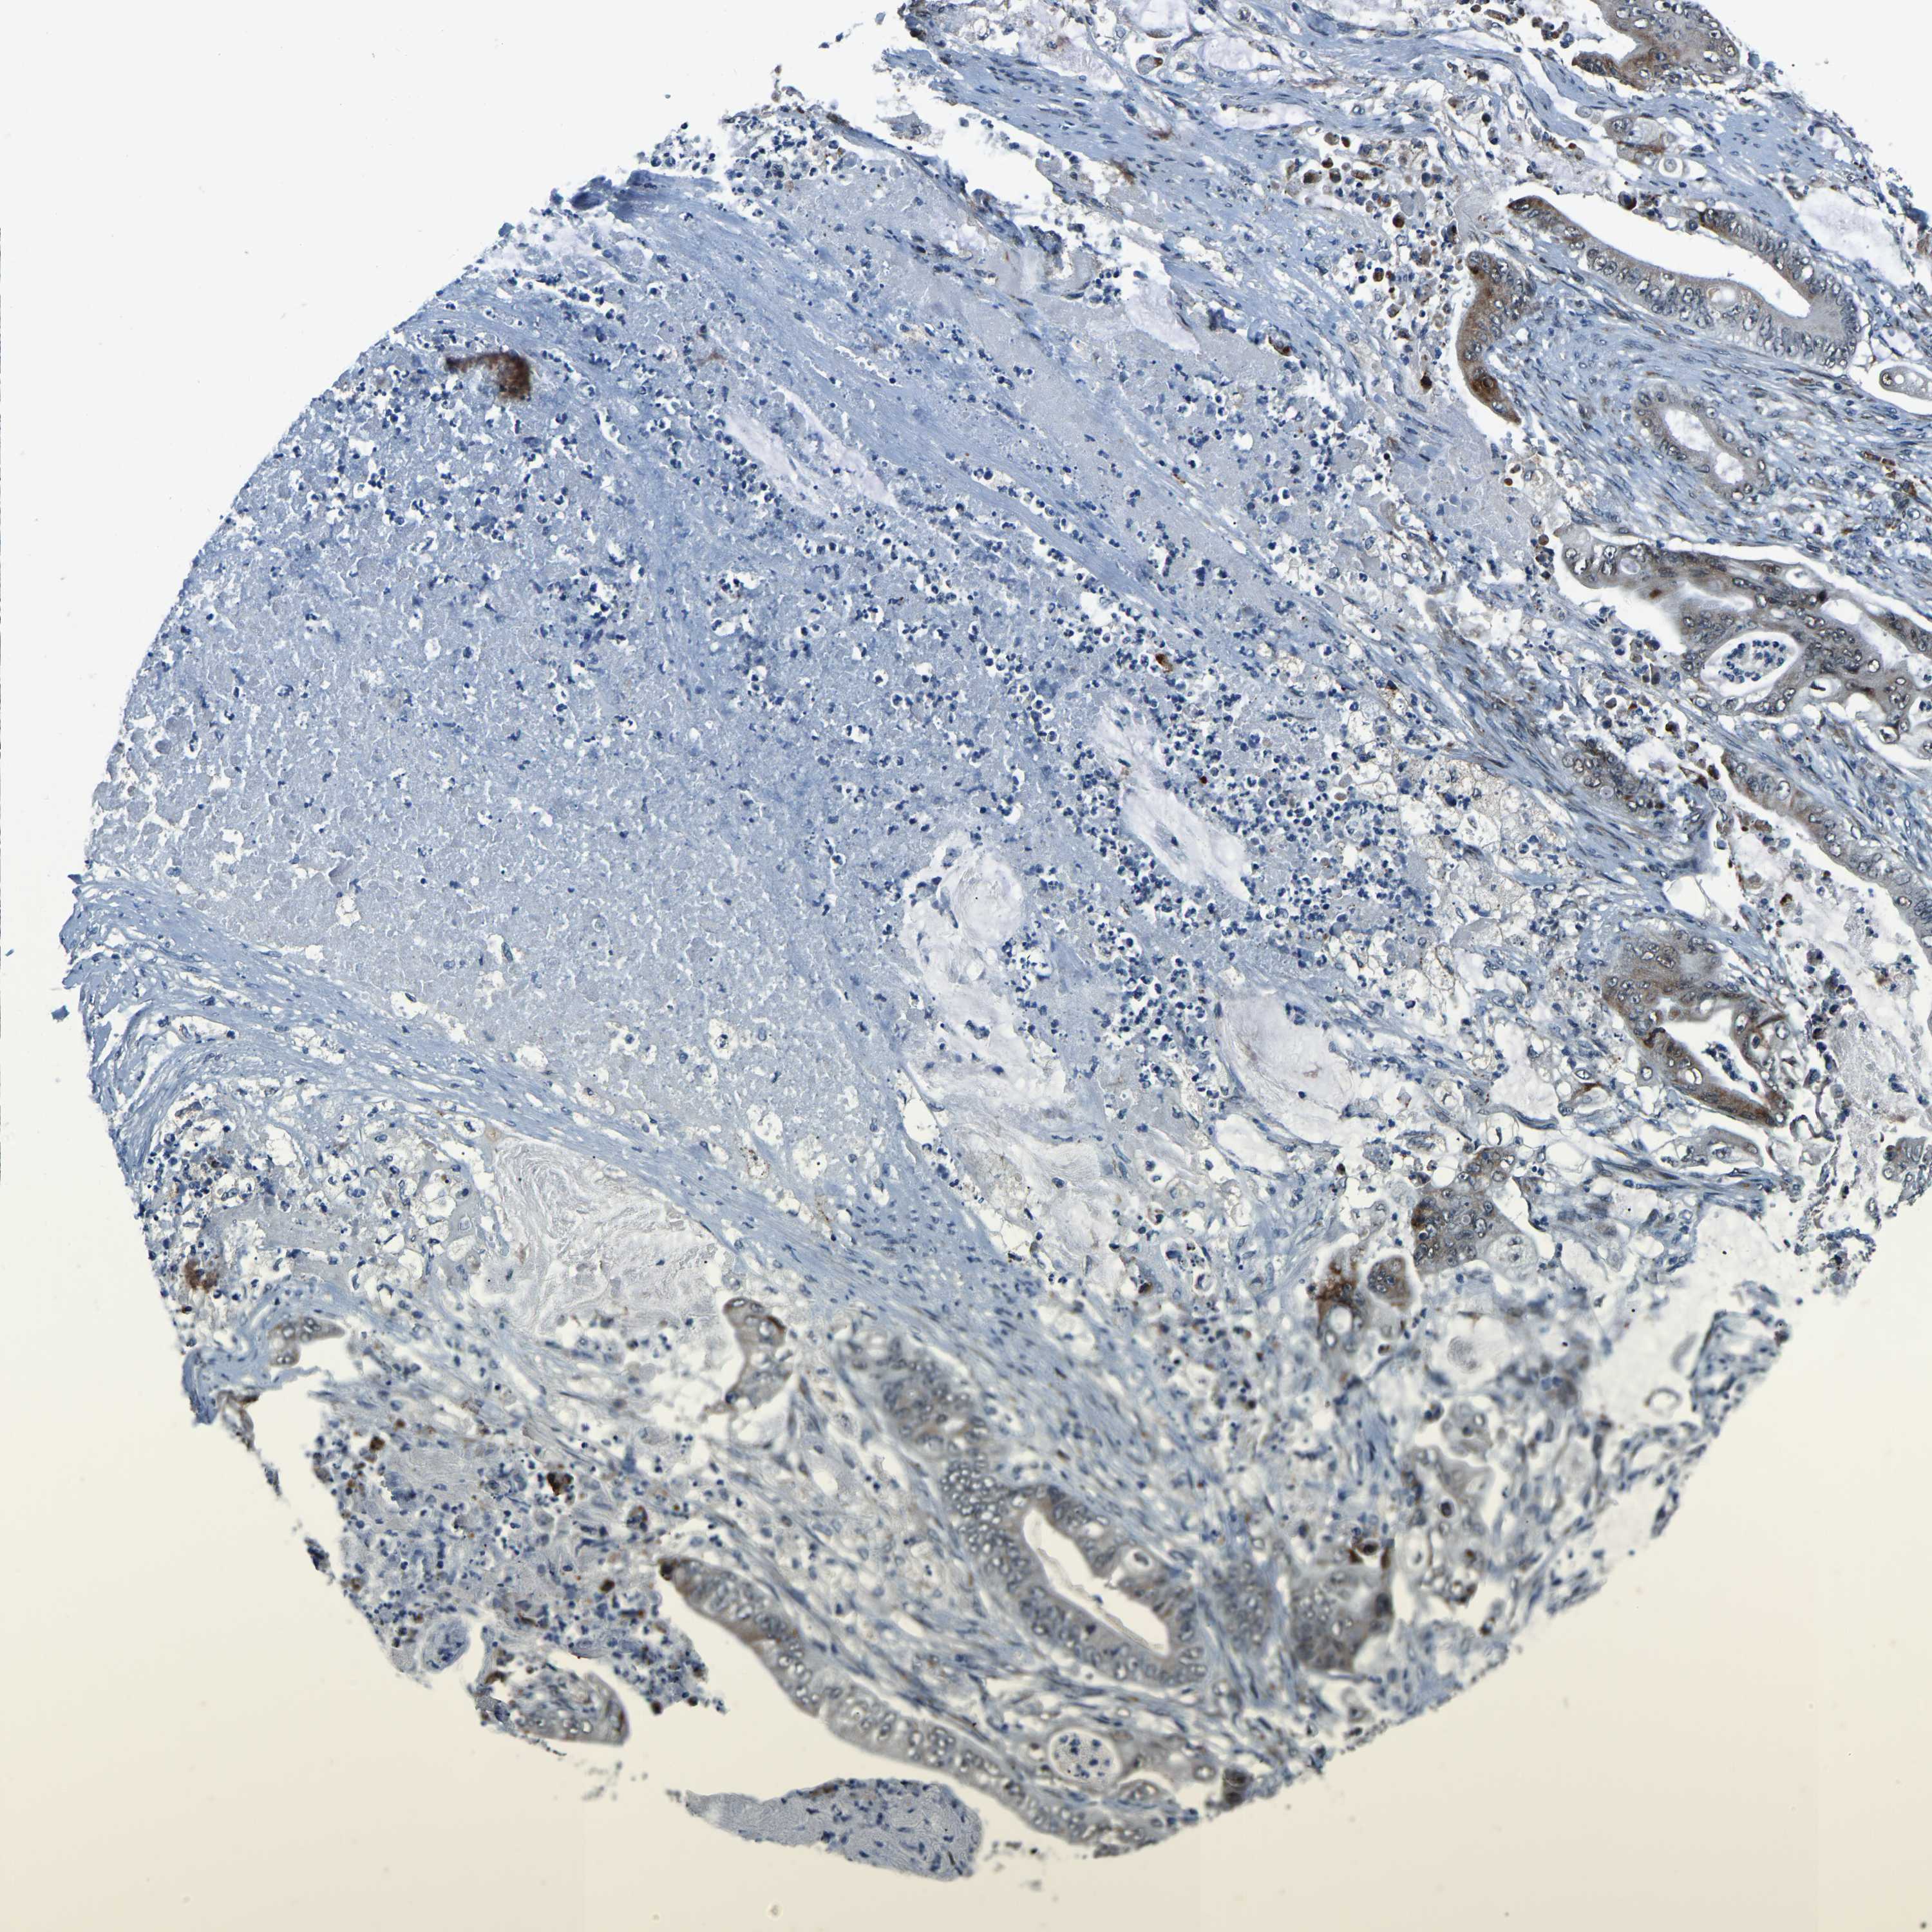

STOMACH CANCER - Protein expressioni

A mouse-over function shows sample information and annotation data. Click on an image to view it in a full screen mode. Samples can be filtered based on level of antibody staining by selecting one or several of the following categories: high, medium, low and not detected. The assay and annotation is described here.

Antibody stainingi

Antibody staining in the annotated cell types in the current human tissue is reported as not detected, low, medium, or high, based on conventional immunohistochemistry profiling in selected tissues. This score is based on the combination of the staining intensity and fraction of stained cells.

Each image is clickable and will lead to virtual microscopy that enables deeper exploration of all samples and also displays staining intensity scores, fraction scores and subcellular localization as well as patient and tissue information for each sample.

Antibody HPA019486

Antibody HPA021517

Staining

High

Medium

Low

Not detected

Intensity

Strong

Moderate

Weak

Negative

Quantity

>75%

75%-25%

<25%

None

Location

Nuclear

Cytoplasmic/membranous

Cytoplasmic/membranous,nuclear

Adenocarcinoma, NOS